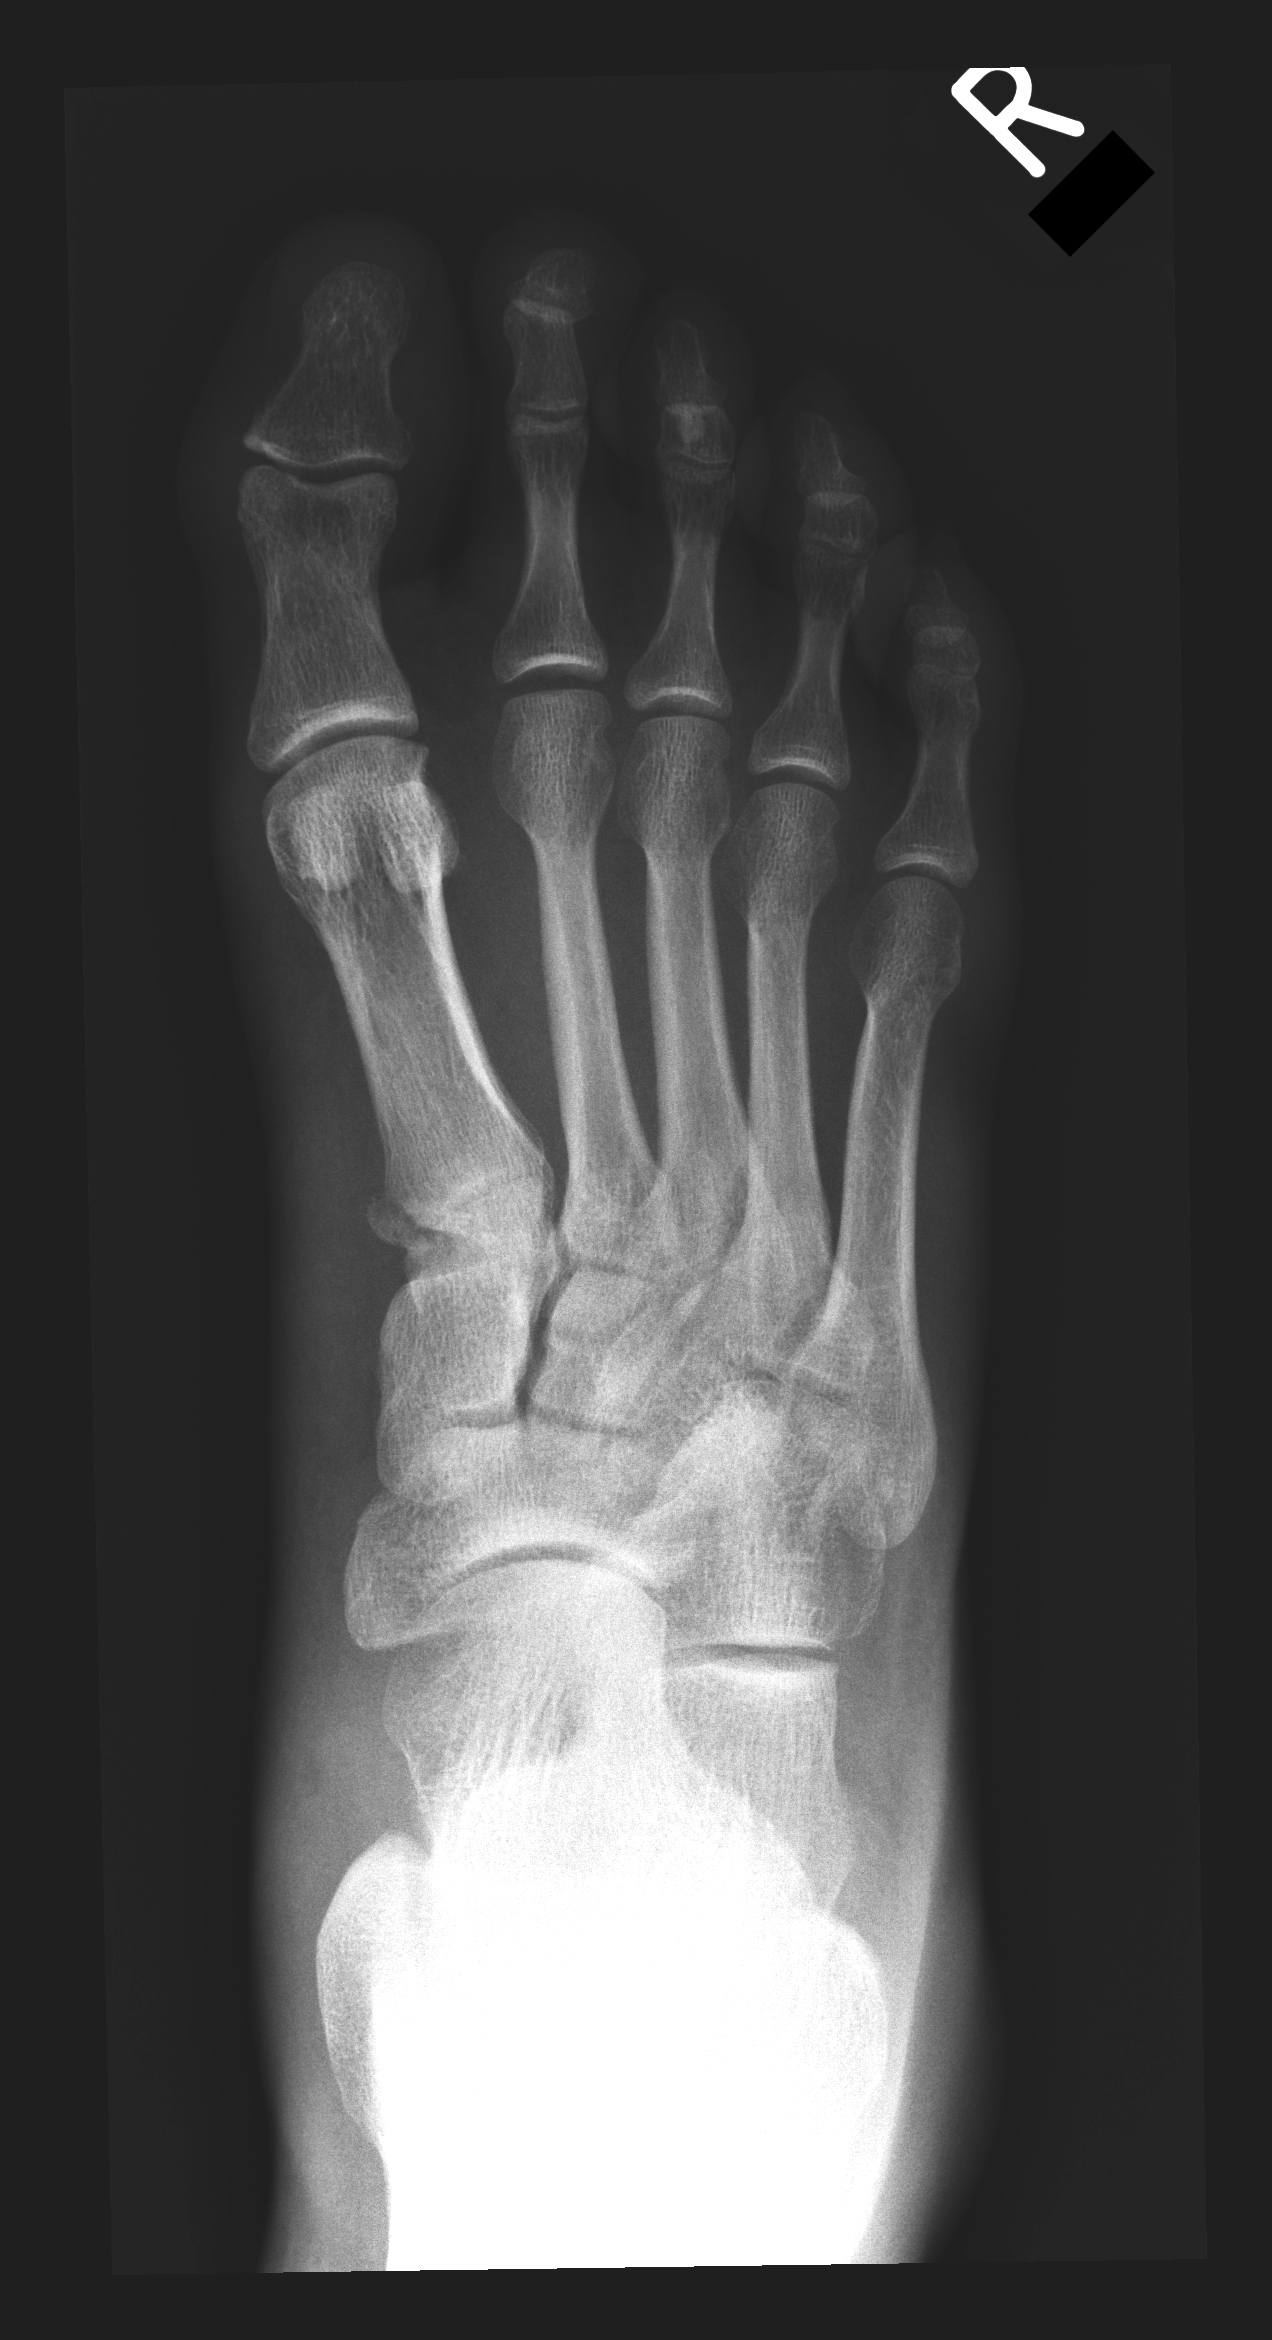

| 25 |

Abnormal fr mp |

Abnormal Left third middle phalanx fracture |

Correct |